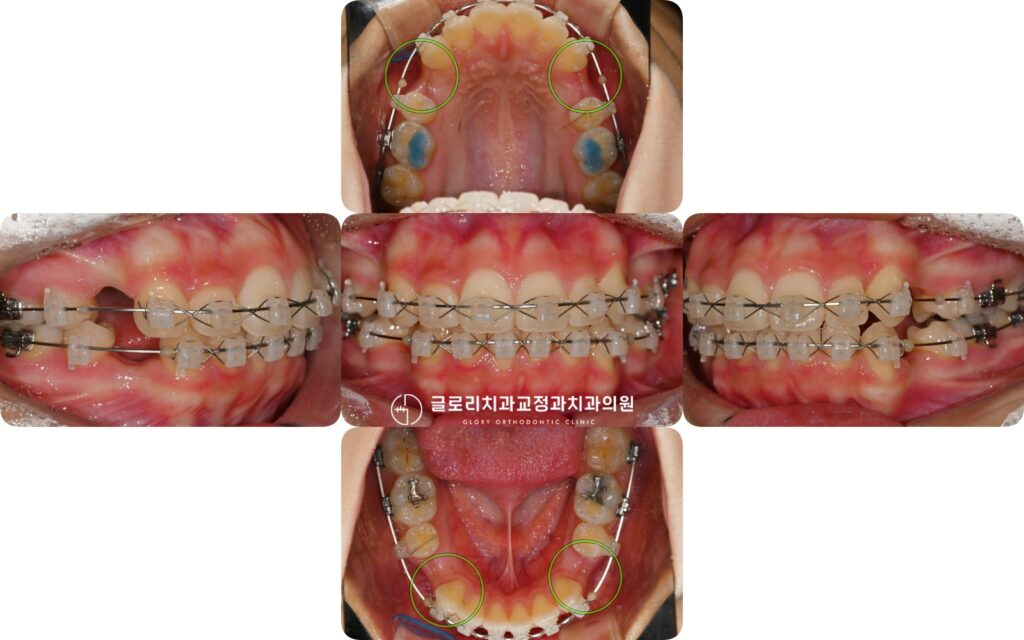

준비된 사진을 살펴보면

교정이 진행되면서 발치 공간이 상당 부분 닫히고

배열이 한층 정돈된 모습을 확인할 수 있습니다.

망우동 교정 치과 에서 보여드리는 변화된 구강의 모습으로

불규칙했던 치열이 가지런히 정렬되었고 깊게 물려있던 과개교합 역시

완화된 것을 알 수 있습니다.